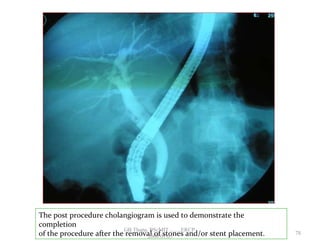

The post procedure cholangiogram is used to demonstrate the

completion

of the procedure after the removal of stones and/or stent placement. 78

• 73.

The post procedurecholangiogram is used to demonstrate the completion of the procedure after the removal of stones and/or stent placement. 78 GB Thapa, BScMIT.........ERCP 2068.01.05